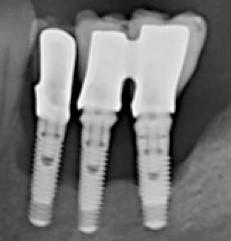

➜ la situation osseuse « PA » (Peri-implantitis Apparearance) comprend 5 classes PA0 à PA4 (fig. 3 à 6). établies selon les critères suivants: le nombre d’implants adjacents atteints (un seul implant, deux implants, ou au moins trois implants atteints), l’importance de la perte osseuse (selon le pourcentage de la hauteur d’implant qui a perdu de l’os : < 60 % ou > 60 %), le nombre de parois osseuses restantes autour du défaut (aucune, ou au moins une paroi).

Figure 4: exemple de périimplantite PA2c (perte osseuse moins de 60 % de la hauteur implantaire, défaut de 1 à 4 parois avec cratère > 3 mm sur les deux implants)

Figure 5 : exemple de périimplantite PA3a (perte osseuse < 50 % de la hauteur des implants adjacents séparés de moins de 3 mm, avec ou sans cratère)